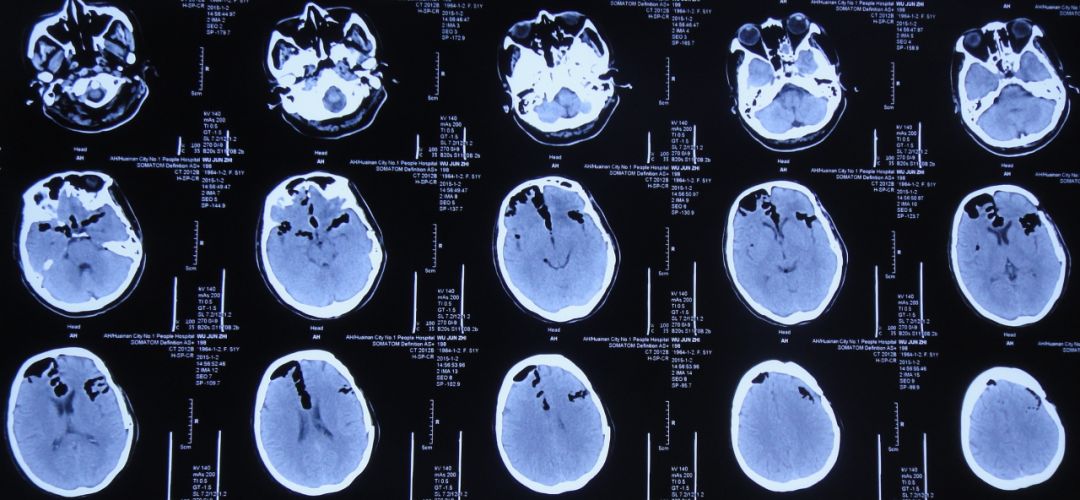

患者女,50岁,安徽省淮北市人。2014年12月14日,患者因高处坠落伤(2米左右)伤及头胸部及四肢,致昏迷,左耳、左鼻流血性液体,急诊前往安徽省淮南市潘集区某医院急查头CT显示左额叶脑挫伤、左侧颞骨凹陷性骨折、脑肿胀、颅内积气(图1);眼眶CT显示双侧眼眶内侧壁骨折(图2);胸部CT显示左侧肋骨骨折伴肺挫伤;右上肢X片显示右桡骨远端粉碎性骨折;左肩部X片显示左侧锁骨骨折。立即给予住院,保守治疗。

图1:2014年12月14日头CT:左额叶脑挫伤、左侧颞骨凹陷性骨折、脑肿胀、颅内积气